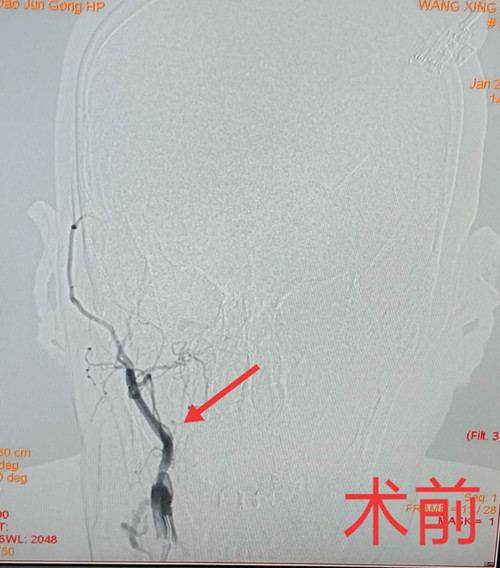

在秦皇岛军工医院神经内科住院患者王某,通过全脑血管造影发现,发生急性梗死的大脑组织是依靠侧枝循环来维持血供的,原供血的颈内动脉已完全闭塞,而且侧枝代偿血管有阶段性重度狭窄,一旦再发生闭塞,患者脑梗塞的面积将进一步扩大,症状会更加严重,甚至危及生命。好在患者只存在较小的神经功能损伤,症状表现为阵发性的头晕和左侧肢体肌力减弱,没有影响到日常生活。如果此时能打通闭塞的颈内动脉,恢复原有供血通道,不但能缓解患者的症状,还能避免再次发生梗塞的风险,提高今后患者的生活质量。李光雷副主任与家属做了详细的病情介绍和沟通后,同意行经皮穿刺右侧颈内动脉闭塞开通术。

手术方案确定后,在神经外科、麻醉科、急诊介入中心的全力配合下,在天坛医院高峰教授的指导下,手术过程历时1个半小时,经过导丝穿通、球囊扩张、血管保护、支架置入一系列的细致操作,患者的颈内动脉完全开通,开通长度达10厘米。术后头CT未见出血,血压控制稳定,安全度过了高灌注风险期,术后三天患者顺利出院。